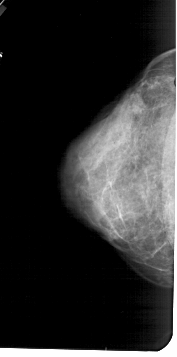

A_1570_1.LEFT_CC

LEFT_CC LINES 4996 PIXELS_PER_LINE 2476 BITS_PER_PIXEL 12 RESOLUTION 43.5 NON_OVERLAY